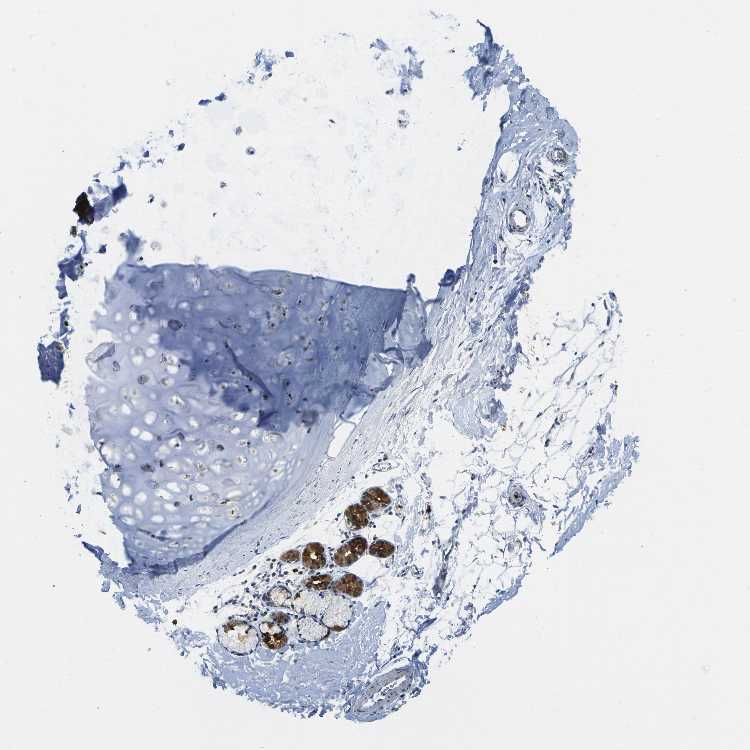

SOFT TISSUE 2 - Antibody stainingi

Antibody staining in the annotated cell types in the current human tissue is reported as not detected, low, medium, or high, based on conventional immunohistochemistry profiling in selected tissues. This score is based on the combination of the staining intensity and fraction of stained cells.

Each image is clickable and will lead to virtual microscopy that enables deeper exploration of all samples and also displays staining intensity scores, fraction scores and subcellular localization as well as patient and tissue information for each sample.

Antibody HPA017076

Fibroblasts Not detected

Peripheral nerve Not detected